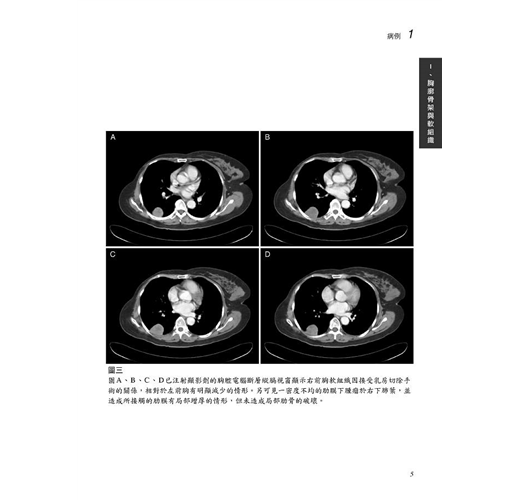

病例1 轉移性肉瘤(Metastatic sarcoma) 3

病例2 男性乳癌(Male breast cancer) 9